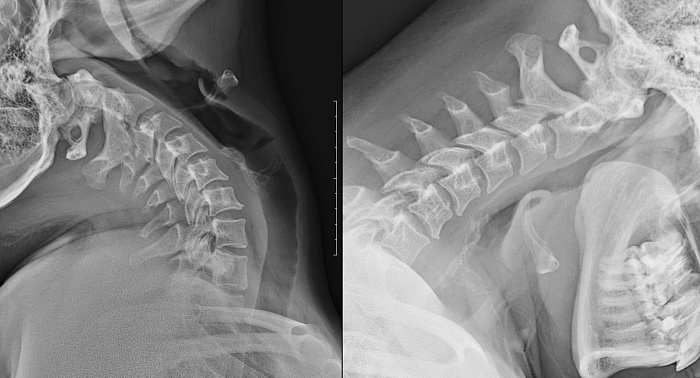

Рентгенография одного отдела позвоночника: функциональные пробы Рентгенография одного отдела позвоночника: функциональные пробы

Рентгенография одного отдела позвоночника: функциональные пробы – важный метод скринингового исследования, который позволяет оценить состояние отдела позвоночника.

Диагностическая услуга выполняется в двух проекциях.

18.7 Рентгенография (цифровая) одного отдела позвоночника: функциональные пробы (сгибание, разгибание, запись на диск) 3 600 ₽